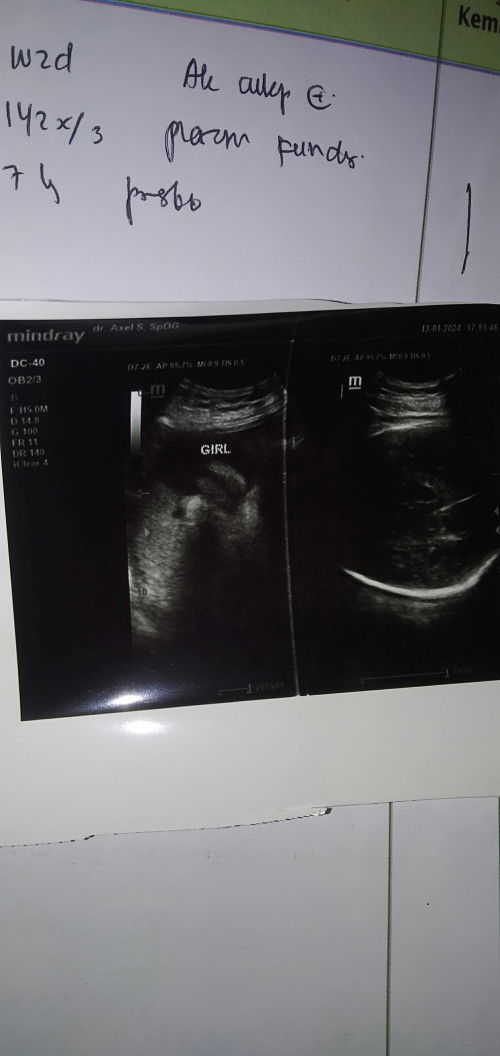

Bu mau tanya apa ini jenis kelamin perempuan......dokter sih bilang cewe tpi aku masih ragu apa ada yg sma

Mau tanya nih aku kan tdi abis USG apa ini Dede bayinya ya dan jenisnya cwe atau cwo ya

Pas USG katanya ketutupan kaki